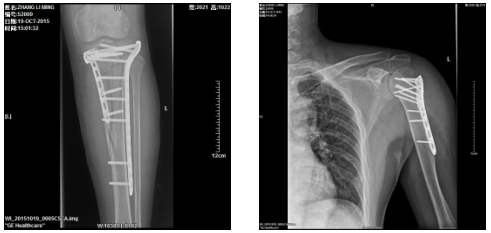

3、复杂性关节内骨折的内固定手术。

6、四肢骨折的复位内固定术。